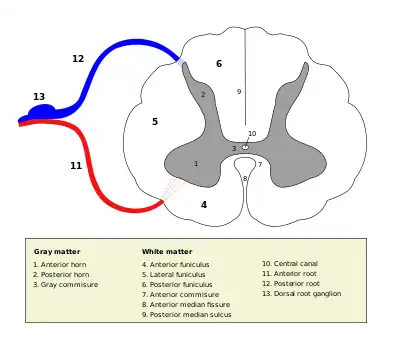

Cross section of the spinal cord. The posterior horn is the upper protrusion of grey matter, labeled with "2" | |

The posterior grey column (posterior cornu, dorsal horn, spinal dorsal horn, posterior horn, sensory horn[1]) of the spinal cord is one of the three grey columns of the spinal cord. It is a pronounced, dorsolaterally-oriented ridge of gray matter in either lateral half of the spinal cord. When viewed in transverse section, it is termed the posterior horn or dorsal horn.[2]

The posterior column contains the cell bodies of second-order sensory neurons and their synapses with the pseudounipolar first-order sensory neurons (whose cell bodies are located within the sensory ganglia (a.k.a. dorsal root ganglia)). It receives several types of sensory information from parts of the body (including fine touch, proprioception, and vibration) from receptors of in the skin, bones, and joints.

The posterior grey column is subdivided into six layers termed Rexed laminae I-VI

- Marginal nucleus of spinal cord (lamina I)

- Substantia gelatinosa of Rolando (lamina II)

- Nucleus proprius (laminae III, IV)

- Spinal lamina V, the neck of the posterior horn[4]

- Spinal lamina VI, the base of the posterior horn.

The other four Rexed laminae are located in the other two grey columns in the spinal cord.